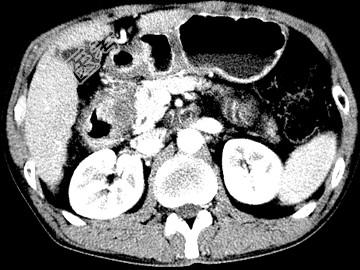

- 单项选择题女,63岁, 右上腹疼痛,呈不规律性钝痛, 伴恶心,时有呕吐, 呕吐物为胃内容物混有胆汁,CT检查如图, 最可能的诊断是 ( )

A、十二指肠克罗恩病

B、十二指肠结核

C、十二指肠癌

D、十二指肠淋巴瘤

E、十二指肠平滑肌瘤